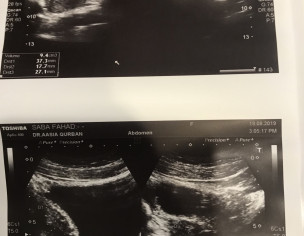

Asking for Self, Female, 27 years old, Rawalpindi

2 doc told me that i have ovarian cysts one doc said that no cysts. Please see and help is there any cyst?

Attach Photo here: